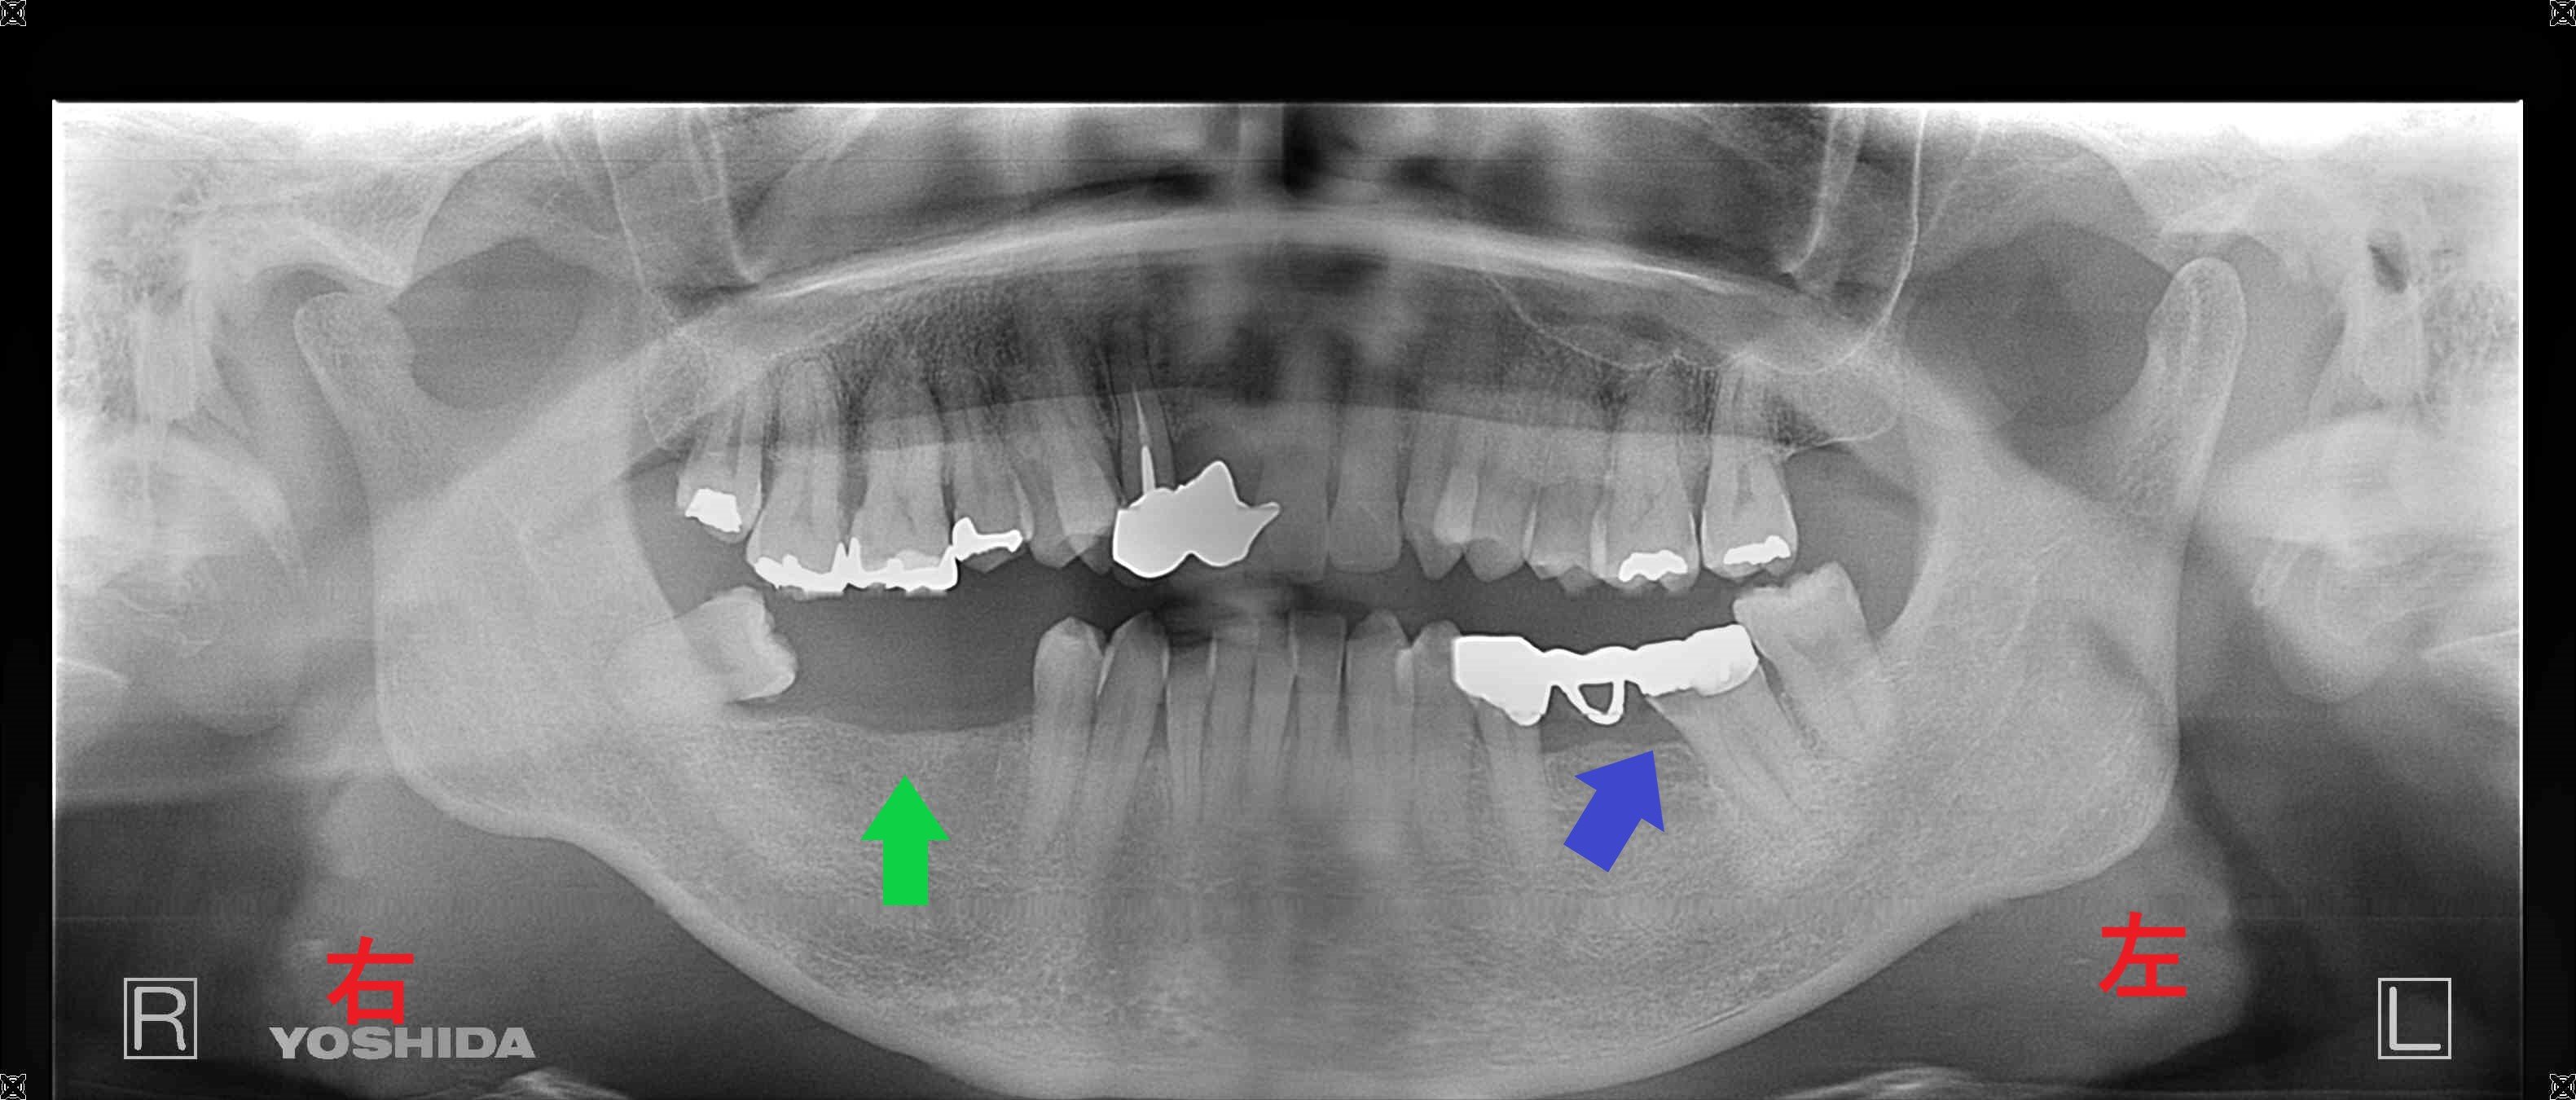

上記の写真は、兵庫県三木市にお住まいの患者様の初診時レントゲン写真です。右下奥歯(緑色矢印)へのインプラント治療を希望されて、当院にご来院されました。写真掲載については、患者様ご本人の同意をいただいております。

インプラントのご説明の前に、右下の青色矢印にご注目ください。こちらには、2本の歯で3本分の被せ物を支える「ブリッジ」という固定式装置が入っていましたが、後方の歯に大きな虫歯(カリエス)が再発しています(これを「2次カリエス」と呼びます)。